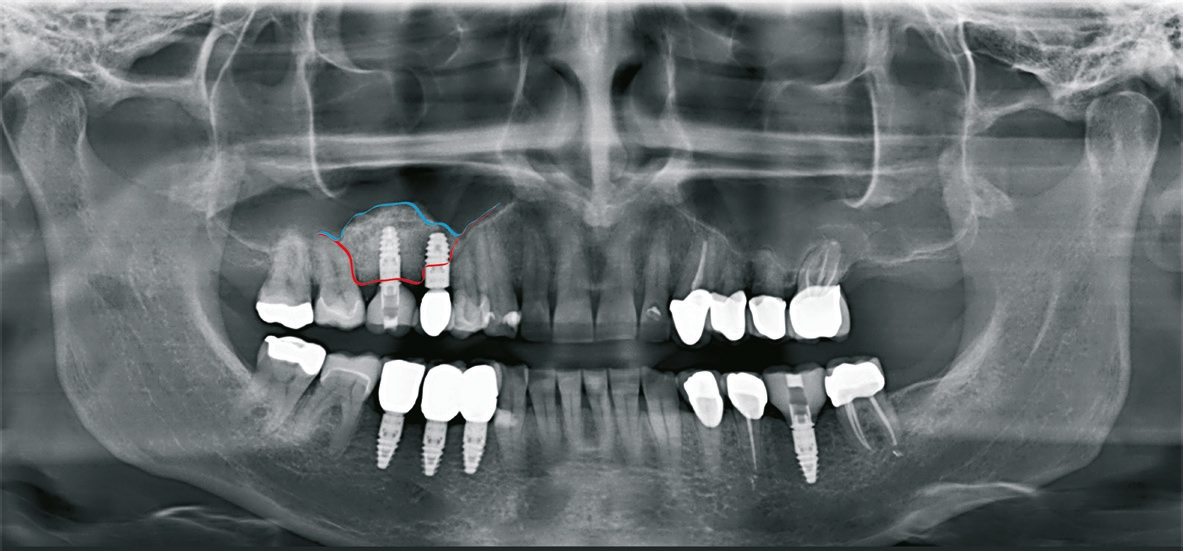

Patient 3: weiblich, 62 Jahre alt, Anamnese: unauffällig; spezielle Anamnese: Zustand nach chronischer schwerer Parodontitis; Diagnose: nicht erhaltungswürdiger Zahn 16, Freiendsituation. Knochenersatzmaterial: maxgraft® (botiss) (Abb. 13 bis 15).

Dr. van Orten